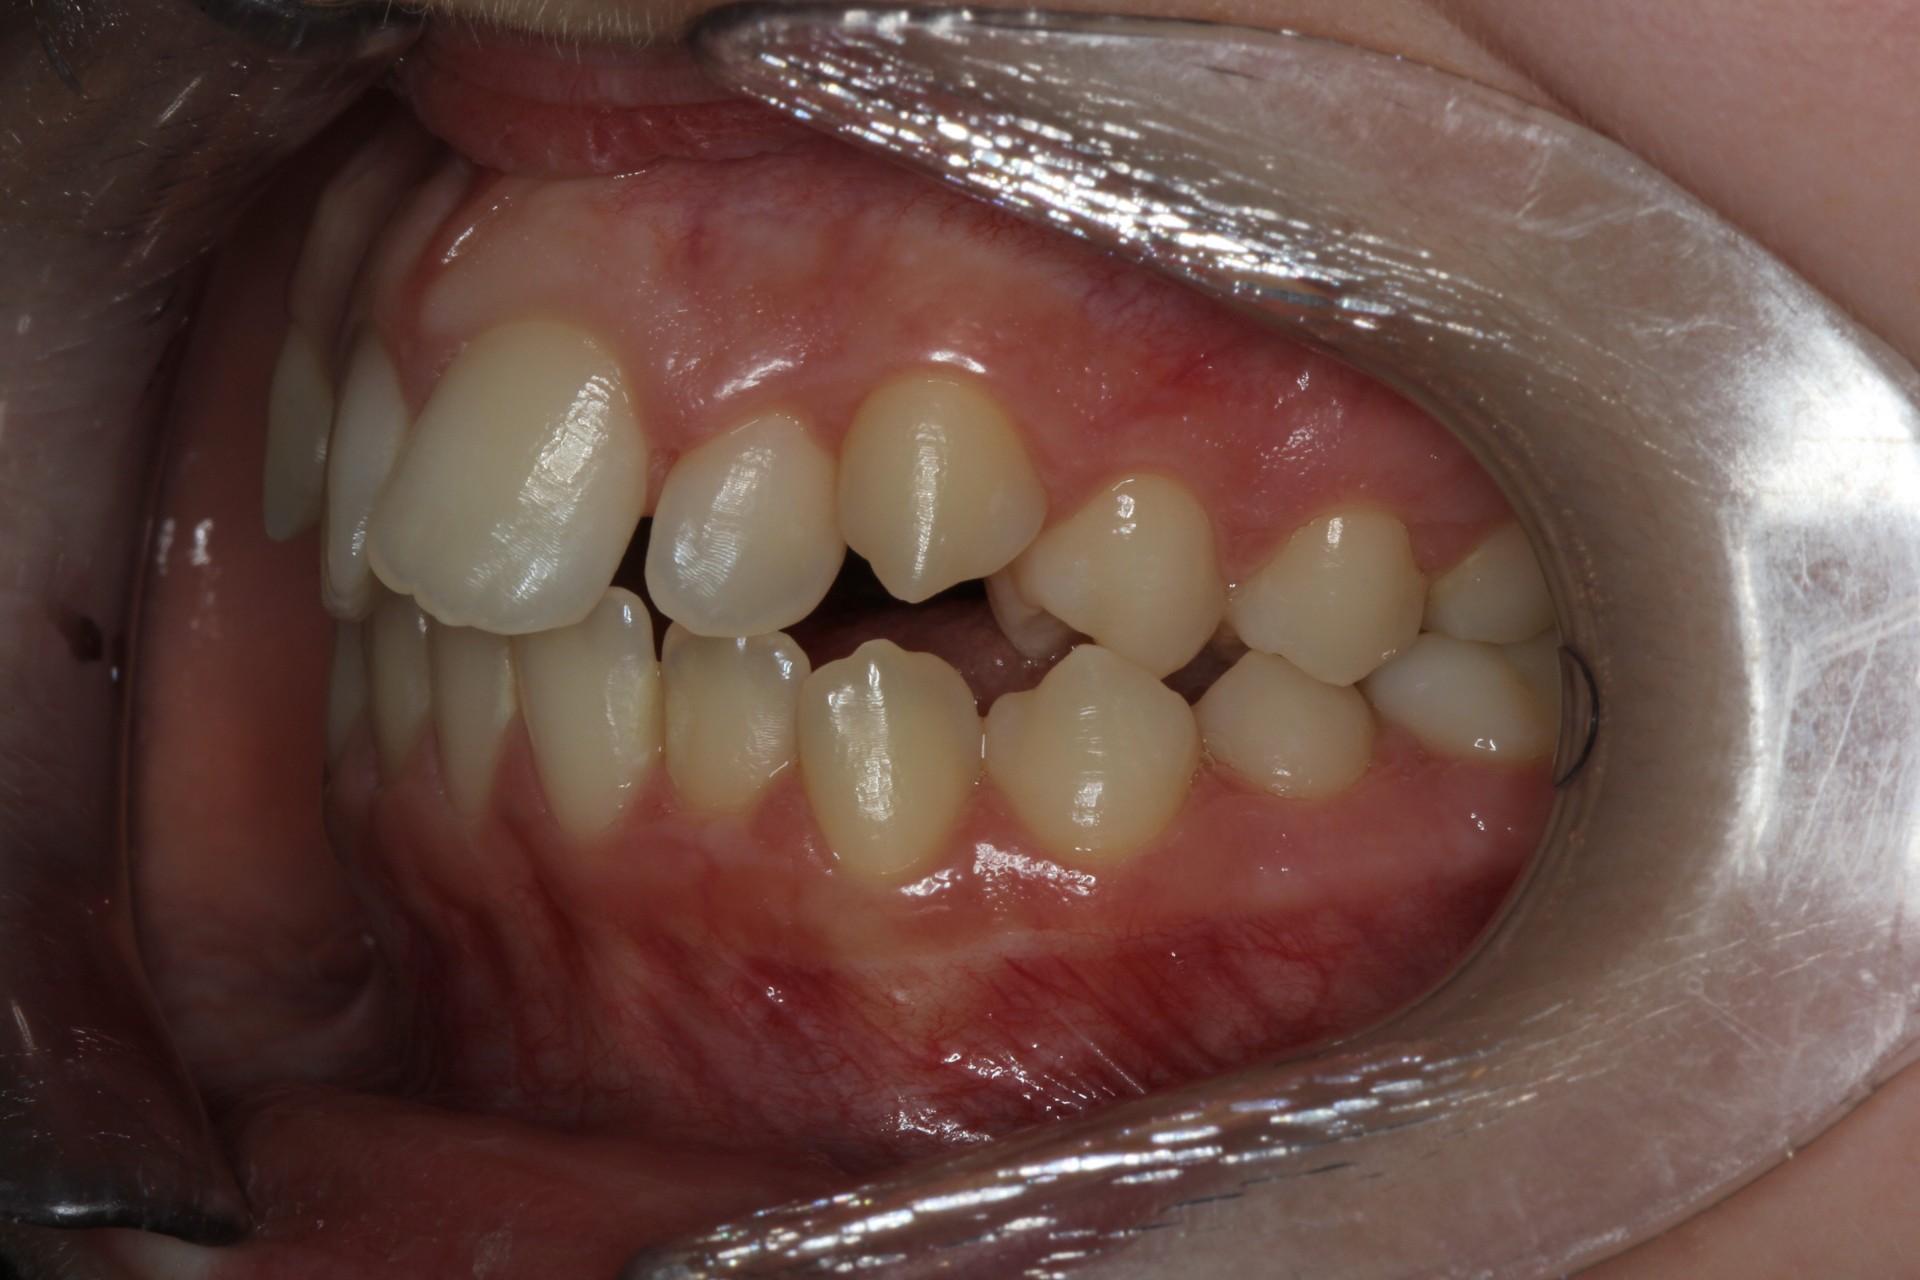

Crowding – Child case